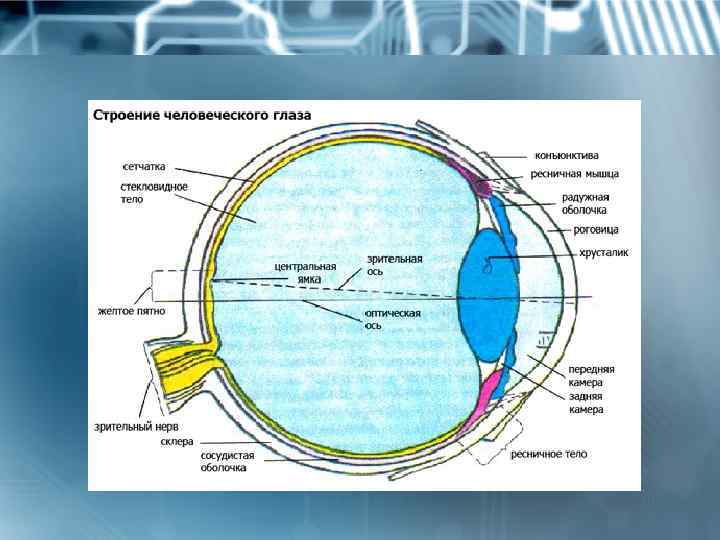

КТ-графики и изображение строения глаза